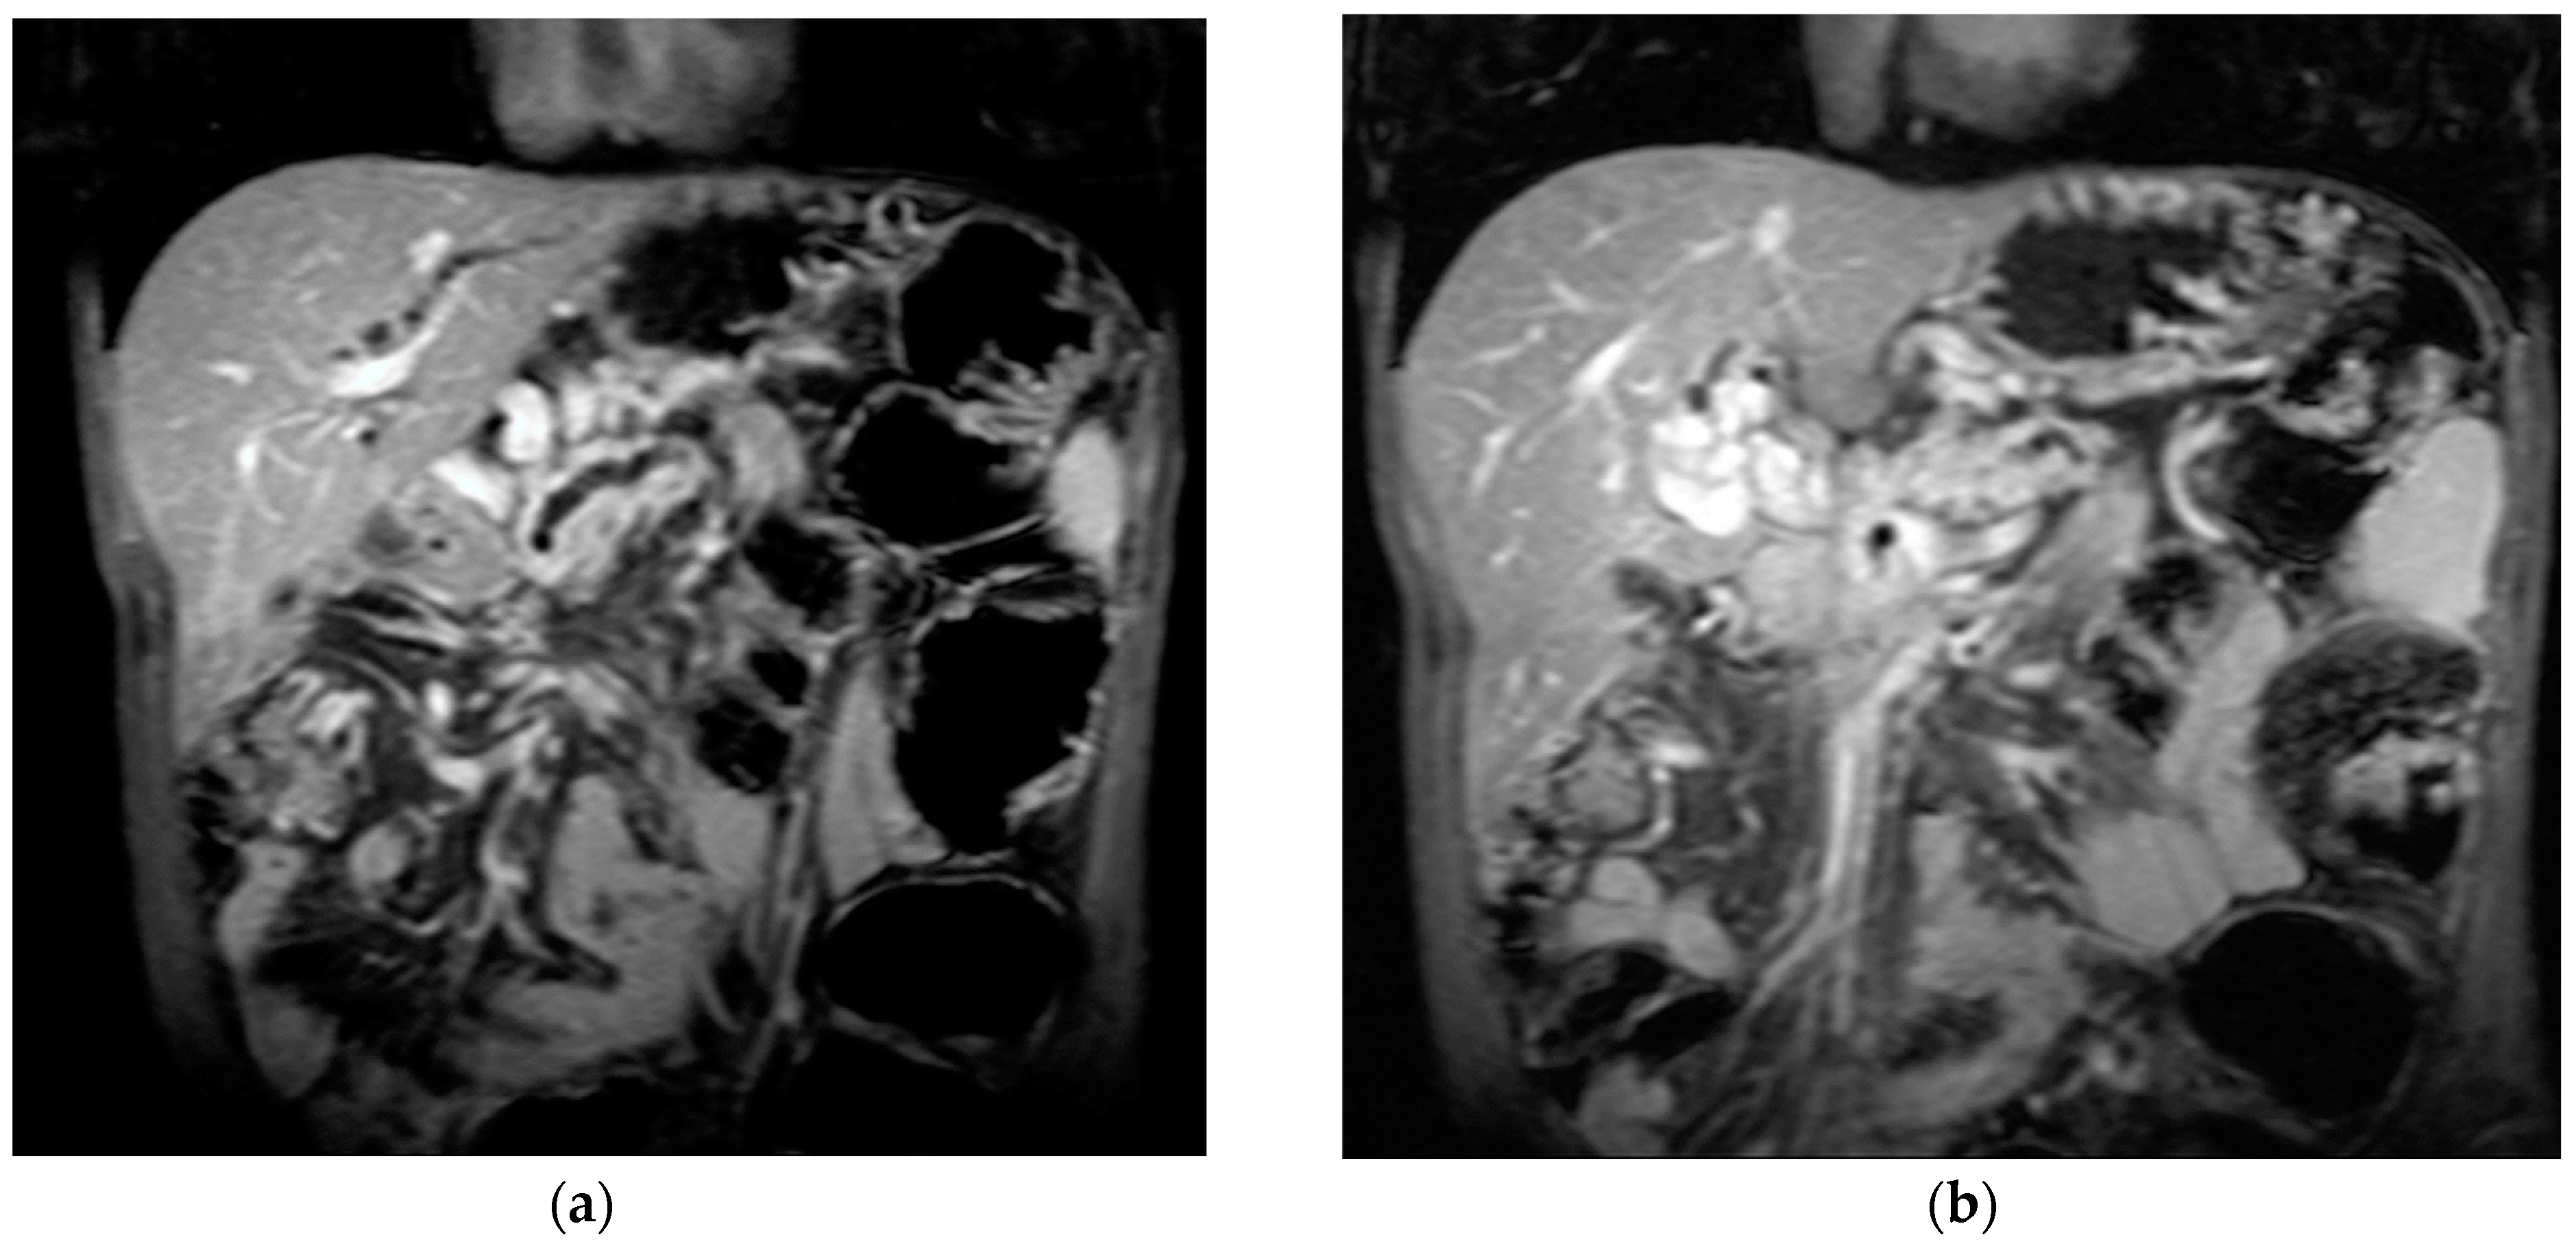

The diagnosis of PVT and PC is made by imaging procedures (transabdominal ultrasound with a Doppler or contrast-enhancing computed tomography scan, magnetic resonance imaging, or angiography in the case of therapeutic intended procedures) [1,3,12,13,14,21,29]. Transabdominal ultrasound is a reliable procedure in 60–100% of cases, with an anechoic aspect in recent cases (requiring Doppler examination or CEUS) and a hypoechoic or hyperechoic aspect in chronic cases [22,29]. Doppler examination may show an anechoic or hypoechoic thrombus and a slower (<15 cm/sec) or absent portal blood flow, and is considered the gold standard (color Doppler) for the diagnosis of PC [1], with a sensitivity and specificity of 95% (Figure 1 and Figure 2) [22]. CEUS can help the diagnosis of benign or malignant PVT, can characterize associated focal liver lesions [30], allows a better characterization of PVT [31], and also permits better detection of PC—Figure 3 and Figure 4 [32]. CT scan and MRI (Figure 5 and Figure 6) are more accurate for the evaluation of liver causes (HCC, abscesses, and other tumors) or other local causes (pancreatitis, diverticulitis, and appendicitis), and for complications (bowel infarction or perforation), and may show permeability of the portal venous system and the flow direction [1,22]. Malignant PVT has intra-thrombus arterial signals on CT, MRI, and/or CEUS, with portal vein diameter frequently 23 mm or above, and with the presence of the tumor at imaging examination (Figure 4 and Figure 6) [21].

Figure 3.

CT scan in a patient with recent surgery for transverse colon adenocarcinoma. (a) The enlarged portal vein, with intraluminal thrombus and peri-gastric collateral circulation, indicated by black arrow. (b) A 59/34 mm portal cavernoma, indicated by black arrow.

Figure 4.

MRI scan in a patient with pancreatic carcinoma. (a) Enlarged portal vein, with intraluminal thrombus. (b) A hilar 5.1/3.3 cm portal cavernoma.

Transabdominal ultrasound with Doppler protocol (Figure 1a,b and Figure 2a,b), CT scan (Figure 3a,b), and MRI (Figure 4a,b) were used for the diagnosis in 88.9, 75.1, and 15% of cases, respectively. CEUS was used for the diagnosis in 49 cases (25.9%) but in only 29 cases was it used for the evaluation of the thrombus, and in two cases for cavernoma diagnosis (Figure 5a,b and Figure 6a,b).